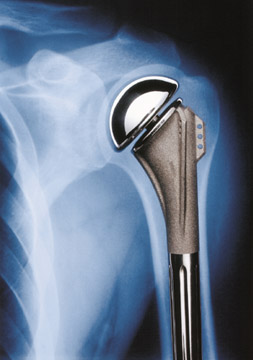

• Die "klassische" Schultergelenkstotalprothese

In einzelnen Fällen ist es möglich durch eine Schultergelenksspiegelung mit Spülung und Reinigung des Schultergelenkes (Arthroskopische Gelenkstoilette) eine gewisse Verbesserung bezüglich Schmerzen zu erzielen. Die Erfolgschancen dieses Eingriffs sind jedoch ungewiss und in zeitlicher Hinsicht nicht voraussagbar. Wenn solche wenig invasive Methoden versagen, muss jedoch eine Kunstgelenkersatzoperation an der Schulter ernsthaft erwogen werden. Je nach Art der Abnutzung kommen hier verschiedene prinzipielle Operationsmethoden und Prothesenmodelle in Frage: